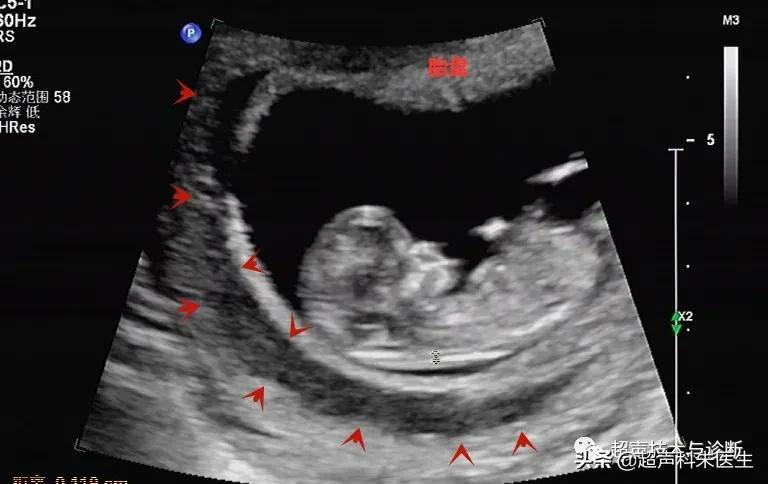

出现绒毛膜下血肿的孕妇,仅有20%会出现阴道不规则流血或下腹部疼痛的症状,而其余大多数绒毛膜下血肿是在超声检查中发现的,其超声表现为:子宫壁和胎膜(或孕囊)之间的无回声区,多位于胎盘下缘至宫颈内口间,以弧形或新月形多见,若血肿较多或血肿形成时间较长时,内可见点、絮状弱回声及条带状强回声,彩色多普勒超声检查:血肿内无血流信号。

接下来我们来看看具体病例:

绒毛膜下血肿需要关注和羊膜绒毛膜未融合以及胎盘早剥进行鉴别。①羊膜绒毛膜未融合是一种现象,在妊娠初期,胚外体腔相对较大,而羊膜囊和卵黄囊均较小,而随着胚胎的发育,羊膜囊逐渐增大,羊膜与绒毛膜越来越靠近,胚外体腔也随之减小,于14周左右羊膜与绒毛膜相互融合,此时胚外体腔消失,若14周后羊膜与绒毛膜之间的距离≥3mm,此情况即为羊膜绒毛膜未融合。②胎盘早剥发病急,有腹痛,血肿位于胎盘后方与子宫壁之间。